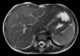

Esophageal leiomyomatosis

A leiomyoma, also known as fibroids, is a benign smooth muscle tumor that very rarely becomes cancer (0.1%). They can occur in any organ, but the most common forms occur in the uterus, small bowel, and the esophagus. [Source: Wikipedia ]